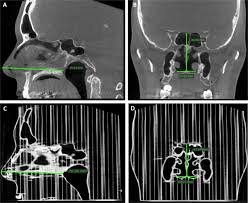

Each cavity is the continuation of one of the two nostrils. The nasal cavity lies just behind the two nostrils and forms the interiors of the nose. The nasal cavity is the are inside the nose, separated from the oral cavity (the area inside the mouth) by the nasal spine. Their locations and structures are best viewed when the head is shown in sagittal section. Protruding prominently from the face, the nose serves as a vent for air exchange. Browse 536 nasal cavity stock photos and images available, or search for nasal cavity diagram to find more great stock photos and pictures. Luckily, there are many ways to clear congestion and increase comfort when a cold or allergy inevitably hits. This can help your body fight inflammation and speed recovery.

Their locations and structures are best viewed when the head is shown in sagittal section.